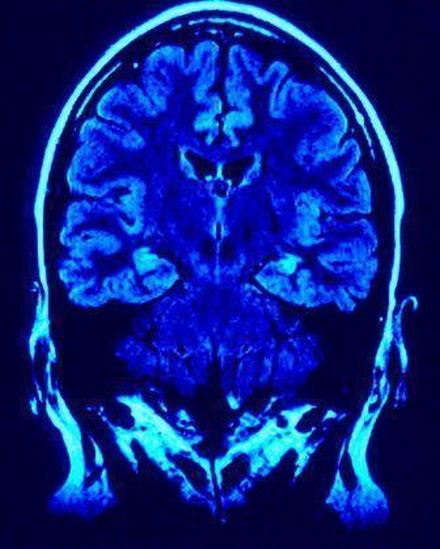

As a result, in order for an injured player or his family to obtain money from this fund, determinations as to the "severity" of the brain injuries will have to be evaluated by "independent doctors working with settlement administrators appointed by the District Court." Of course, this begs the question, what about the players who are only determined to have mild traumatic brain injuries? Where is the line going to be drawn determining the degree of injury for these players?